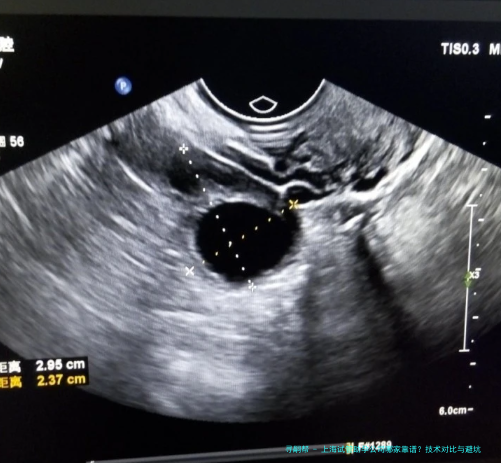

胚胎基因筛查技术是现在的核心角逐力。率先机构已全方位运用PGT-A(染色体检查筛选)与PGT-M(单基因病检查筛选)技术,可检测超200种遗传病,将健康活产率提高40%。

AI与大数据应用正改变传统生殖医疗。先进机构引进AI胚胎评分系统与Time-lapse动态胚胎监测,使优质胚胎筛选准确率提高30%,着床率提高10%-15%。